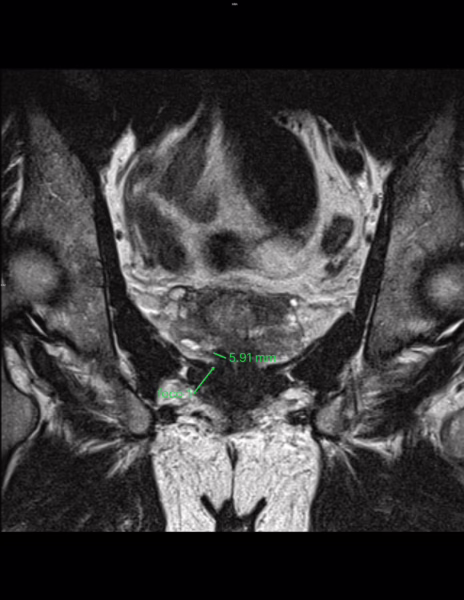

Lesión #1: Mide: aproximadamente 6 mm.

Serie 5, Imagen 22/30.

Localización: Zona periférica posteromedial derecha a nivel apical (sector RA-PZpm).

PEE: Probabilidad de Extensión extraprostática: grado 0 de 3 (Mehralivand).

T2: Hipointensidad menor a 15 mm y sin extensión extraprostática. Categoría 4/5.

DWI: Marcada hiperintensidad en difusión y marcada hipointensidad en ADC. Categoría 4/5.

DCE: no se observa realce focal temprano.

Sin obliteración del ángulo recto prostático.

PI-RADS 4

Lesión índice PI-RADS 4 en la zona periférica posteromedial derecha a nivel apical (sector RA-PZpm). Mide aproximadamente 6 mm, con probabilidad 0 de 3 de presentar extensión extraprostática